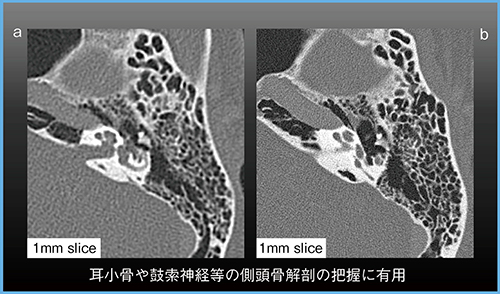

Aquilion Precisionの検出器は0.25mm×160列であり,従来の0.5mm×320列のエリアディテクタCT「Aquilion ONE」と比べて1/4の画素サイズとなる(図1)。当院で実施したスリット状のファントムモデルを用いた視覚的試験では,従来CTよりも高い空間分解能が示され,0.2mmまではより明瞭に描出可能であった。実際の側頭骨の画像でも,Aquilion Precisionの方が耳小骨や乳突蜂巣がより明瞭である(図2)。

図2 Aquilion Precisionによる側頭骨の描出

a:従来CT b:超高精細CT